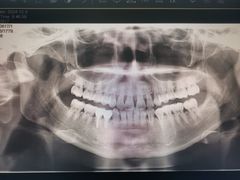

• 上海市徐汇区口腔医院

• -上海市徐汇区口腔医院